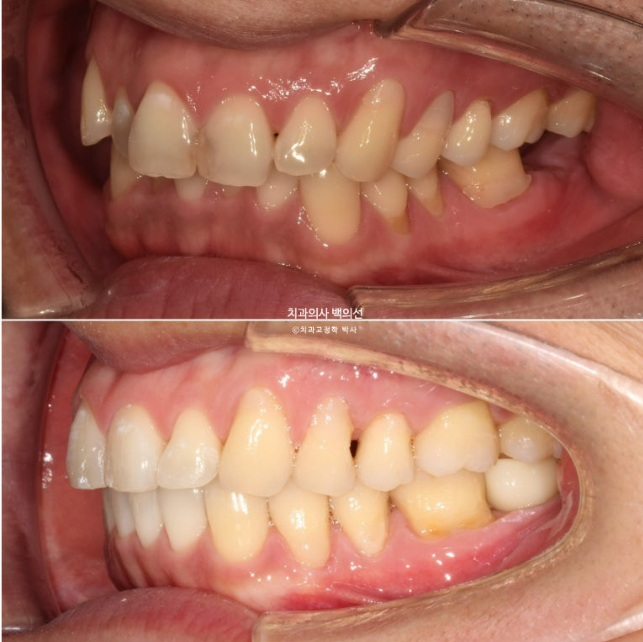

24.05~25.03